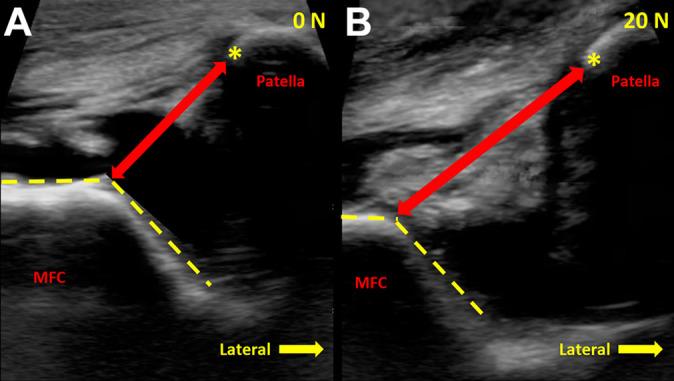

In 10 cadaveric knees, the medial patellofemoral distance was measured to quantify patellar position from 0° to 40° of knee flexion at 10° increments. Knees were evaluated at each flexion angle under unloaded conditions and with 20 N of laterally directed force on the patella to mimic the glide test. Patellar position measurements were made on ultrasound images obtained before and after MPFC transection and compared for significant differences. To determine the ability of medial patellofemoral measurements to differentiate between MPFC-intact and MPFC-deficient states, area under the receiver operating characteristic (ROC) curve analysis and the Delong test were used. The optimal cutoff value to distinguish between the deficient and intact states was determined using the Youden statistic.

A significant increase in medial patellofemoral distance was observed in the MPFC-deficient state as compared with the intact state at all flexion angles ( = .005 to < .001). When compared with the intact state, MPFC deficiency increased medial patellofemoral distance by 32.8% (6 mm) at 20° of knee flexion under 20-N load. Based on ROC analysis and the statistic, the optimal threshold for identifying MPFC injury was 19.2 mm of medial patellofemoral distance at 20° of flexion under dynamic loading conditions (area under the ROC curve = 0.93, sensitivity = 77.8%, specificity = 100%, accuracy = 88.9%).

对10具尸体膝关节,以10°的增量测量髌股内侧距离,以量化膝关节从0°到40°屈曲时的髌骨位置。在每个屈曲角度下,分别在无负荷条件下以及对髌骨施加20 N侧向力以模拟滑动试验的情况下对膝关节进行评估。在MPFC横断前后获取的超声图像上进行髌骨位置测量,并比较有无显著差异。为了确定髌股内侧测量区分MPFC完整和MPFC缺陷状态的能力,使用了受试者操作特征(ROC)曲线分析下的面积和德龙检验。使用约登统计量确定区分缺陷和完整状态的最佳临界值。

与完整状态相比,在所有屈曲角度下,MPFC缺陷状态下的髌股内侧距离均显著增加(P = 0.005至P < 0.001)。与完整状态相比,在20 N负荷下膝关节屈曲20°时,MPFC缺陷使髌股内侧距离增加了32.8%(6 mm)。基于ROC分析和约登统计量,在动态加载条件下,屈曲20°时识别MPFC损伤的最佳阈值是髌股内侧距离为19.2 mm(ROC曲线下面积 = 0.93,灵敏度 = 77.8%,特异性 = 10